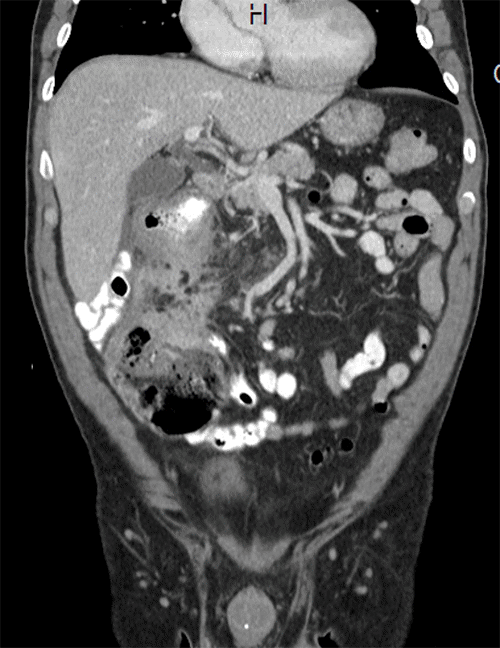

The patient was discussed at our multidisciplinary cancer conference (MDC), and the plan was to repeat the colonoscopy and CT scans. At that time, a repeat CT scan of the abdomen showed progression of the disease, with the mass now measuring 4.3 × 4.3 cm, abutting the inferior vena cava, with multiple enlarged mesenteric lymph nodes. Hepatic lesions concerning for metastases were also found (Figure 3 and Figure 4). Positron emission tomography (PET) scan showed hypermetabolic activity at the hepatic flexure, but PET could not differentiate between malignancy, inflammation, or infectious process. PET also showed nonspecific hypermetabolic liver foci. A repeat colonoscopy showed increased luminal edema, indicating a concerning advancement of the disease (Figure 5). Once again, multiple biopsies were taken, all negative for malignancy. Interventional radiology was consulted to perform a percutaneous biopsy of these new liver lesions; however, at the time of the procedure, no liver lesion was visualized, so a biopsy was not performed.

Figure 3. Second Abdominal CT Scan Showing Right-Sided Colonic Mass, Increasing in Size and Abutting IVC and Duodenum. Published with Permission

Figure 4. Coronal View of Second Abdominal CT Scan. Published with Permission

Right-sided colonic mass, increased in size, abutting the IVC and duodenum